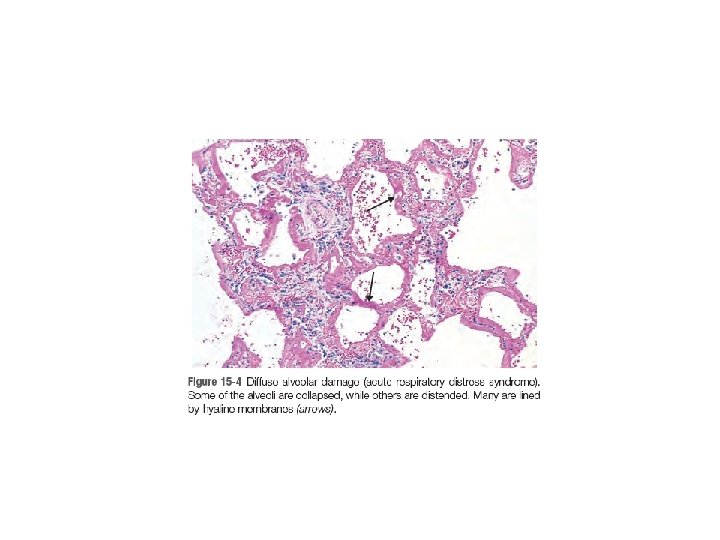

Acute Lung Injury and Acute Respiratory Distress Syndrome (Diffuse Alveolar Damage) • Acute lung injury (ALI) also called noncardiogenic pulmonary edema. • characterized by the abrupt onset of significant hypoxemia and bilateral pulmonary infiltrates in the absence of cardiac failure.

• Acute respiratory distress syndrome (ARDS) is a manifestation of severe ALI. • The histologic manifestation of these diseases is diffuse alveolar damage (DAD).

• Accumulation of intraalveolar fluid and formation of hyaline membranes. Endothelial activation and injury make pulmonary capillaries leaky, allowing interstitial and Intra-alveolar edema fluid to form. Damage and necrosis of type II alveolar pneumocytes leads to surfactant abnormalities, further compromising alveolar gas exchange. Ultimately, the inspissated protein-rich edema fluid and debris from dead alveolar epithelial cells organize into hyaline membranes, a characteristic feature of ALI/ARDS.